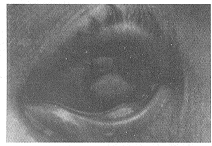

患者 女,56岁,退休工人。双眼痛、视力下降半月。1996年2月16日发现双眼充血,角膜中央灰色,伴有异物感。2周后因角膜黄白色面扩大、疼痛、视力下降,于1996年3月2日入院。患者已有20年糖尿病病史,长期用胰岛素,但血糖仍有波动,无使用激素和受外伤史,无使用任何滴眼液史,无家族性遗传病、眼病及急慢性传染病史。眼部检查:右眼视力0.08,左眼数指/1尺。右眼结膜混合充血(++),左眼(+++),双下睑结膜对应角膜病变区有灰黄色隆起溃疡面(图1),有少许灰白色分泌物。双眼3:00~9:00角膜缘内2mm处可见8mm×3mm长条形黄白色隆起溃疡面,层叠状外观,附有粘稠苔状分泌物,与健康角膜面分界清楚,基质层有浸润(图1)。角膜KP(-),Tyndall征(-)。虹膜纹理清晰。双眼晶状体皮质密度略增高。散瞳可见双眼底后极部“蚤咬状”微血管瘤,点片状出血,累及黄斑,血管屈曲,未见渗出。

图1 治疗前